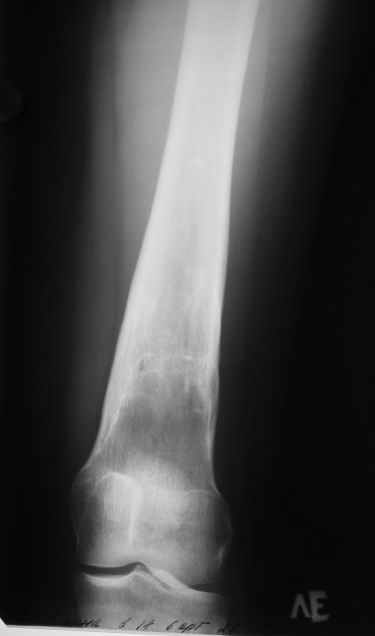

Уважаемые коллеги, приношу извенения за молчание. Готовили материал и боялись писать раньше времени. Все хотели убедиться в том, что после операции все будет спокойно. Спасибо за отклики и советы. К сожалению, гамма-гвоздя, штифтов с возможностью установки более 2-х блокирующих винтов у нас нет. Зато нашли достаточно длинную пластину с угловой стабильностью. После проведения предоперационной подготовки и планирования выполнили остеосинтез. В условиях рентгеноперационной, после репозиции дистрактором из одного разреза 5см в проксимальном отделе подкожно установили пластину. Пришлось выполнить дополнительный разрез до5см в проекции перелома диафиза в средней трети, из которого удалось репонировать перелом и выполнить фиксацию стягивающим винтом. Затем все завершилось наложением пластины с угловой стабильностью. Пластина оказалась достаточно длинной, что позволило перекрыть все переломы с фиксацией каждого отломка минимум 5-ю винтами. Синтез достаточно стабилен. Пациентка активизирована на 3-и сутки(снимки прилагаются). В настоящий момент пациентка выписана на амбулаторное лечение. Еще раз, огромное спасибо всем за помощь в выборе тактики и просто совете. С уважением Украинский Е.

Получилось очень симпатично, мои поздравления. А можно фото конечности без наклеек посмотреть?

И межфрагментарный винт на диафизе - так ли он нужен при выбранном варианте остеосинтеза с относительной стабильностью?